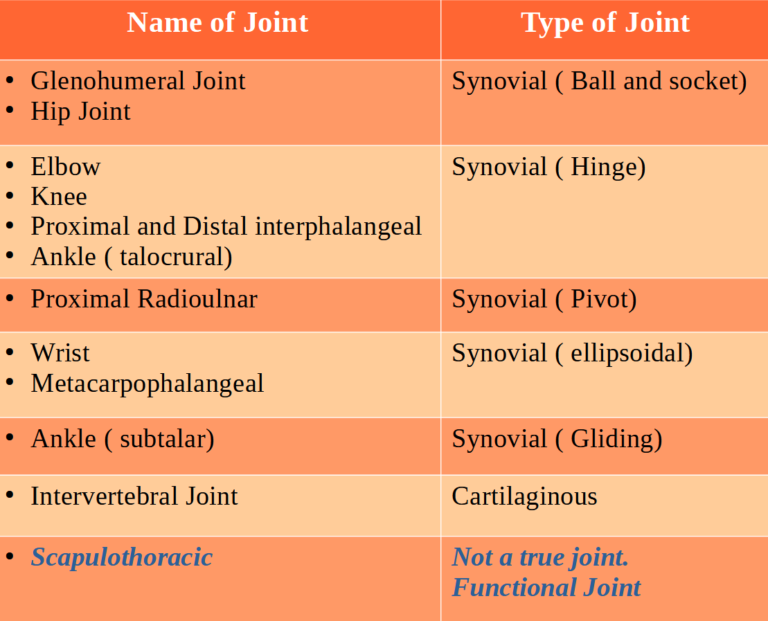

Joints are classified as synarthrodial, amphiarthrodial, or diarthrodial (synovial)

Synovial joints are the most common type of joint in the body . These joints are diarthrodial, meaning they are freely mobile.

A few synovial joints of the body have a fibrocartilage structure located between the articulating bones. This is called an articular disc, which is generally small and oval-shaped, or a meniscus, which is larger and C-shaped. Synovial joints are further classified based on the type of movements they allow.

There classifications are: hinge (elbow), saddle (carpometacarpal joint), planar (acromioclavicular joint), pivot (atlantoaxial joint), condyloid (metacarpophalangeal joint), and ball and socket (hip joint)